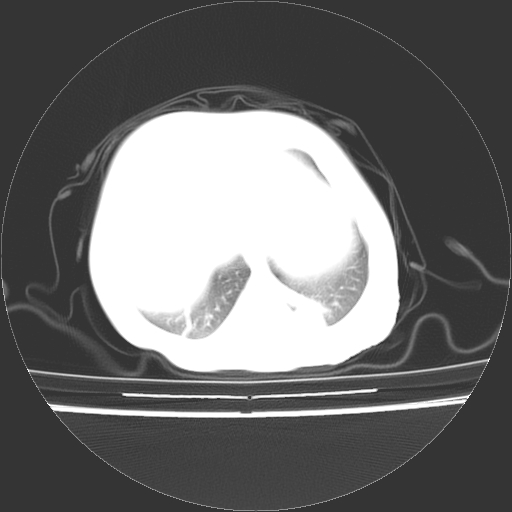

以下是引用余辉在2009-5-8 8:44:00的发言:[br]鸡胸,胸腺肥大,双肺感染性病变,结合病史支原体肺炎可能性大

以下是引用影像之路在2009-5-8 15:46:00的发言:[br]1)胸廓畸形。2)考虑两肺感染性病变,并右肺上中叶肺不张;建议抗炎治疗后复查。3)胸腺肥大。4)前上中纵隔占位性病变待排;建议追踪复查。